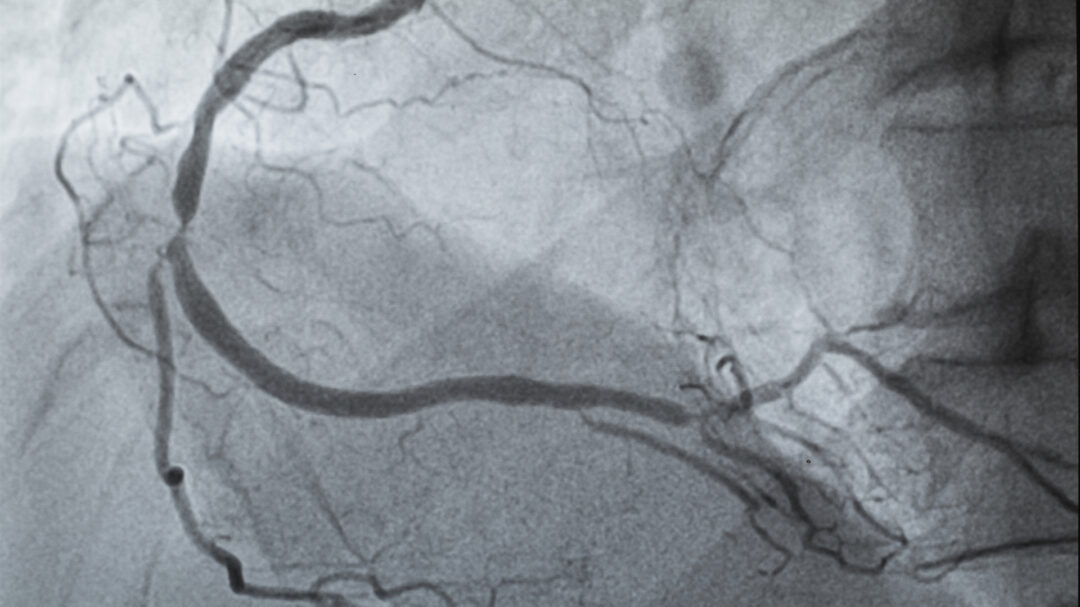

Οι γιατροί συνήθως ελέγχουν την ύπαρξη απόφραξης στις αρτηρίες της καρδιάς με τη βοήθεια της στεφανιογραφίας, μιας επεμβατικής εξέτασης η οποία χρησιμοποιεί χρωστική ουσία και ακτινογραφίες. Κατά την τελευταία δεκαετία, μεγάλες ευρωπαϊκές μελέτες διαπίστωσαν ότι τα ποσοστά στένωσης στα στεφανιαία αγγεία έχουν μειωθεί κατά περίπου 30% τόσο στους άνδρες όσο και στις γυναίκες με συμπτώματα στεφανιαίας νόσου. «Έχουμε δει παρόμοιες τάσεις στα μητρώα της Υπηρεσίας Βετεράνων, της Mayo Clinic και του δικού μας Mass General Brigham, εδώ και περίπου 15 χρόνια», λέει ο δρ DiCarli, ο οποίος είναι εκτελεστικός διευθυντής καρδιαγγειακής απεικόνισης στο Brigham and Women’s Hospital. Αντί για επεμβατικές αγγειογραφίες, στο μητρώο του Mass General Brigham καταγράφονται αποτελέσματα από μια μη επεμβατική απεικονιστική εξέταση που ονομάζεται αξονική στεφανιογραφία. Τα ευρήματα αυτού του μητρώου, το οποίο περιλαμβάνει άτομα κάτω των 65 ετών (αντίθετα με άλλα μητρώα, τα οποία περιλαμβάνουν κυρίως ηλικιωμένους), έδειξαν επίσηςμείωση της αποφρακτικής στεφανιαίας νόσου κατά 30% έως 40% στην πάροδο του χρόνου.